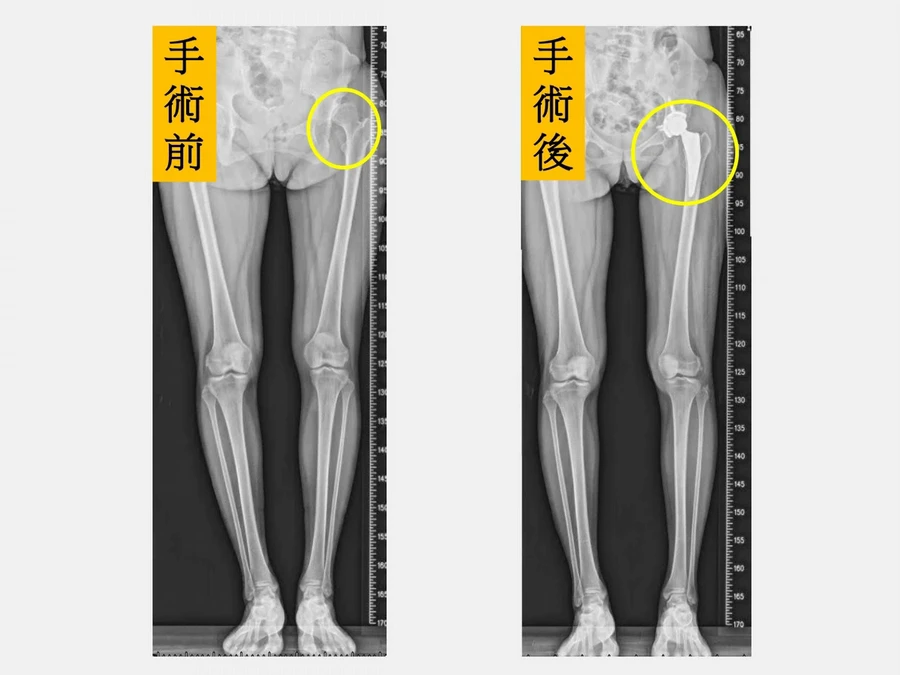

34歲陳小姐因左側髖關節發育不良,幼兒園與小學時曾接受兩次髖關節截骨矯正手術,但走路仍常卡卡、運動後疼痛,活動多時甚至跛行。隨著孩子上小學、參與活動增加,她常需靠止痛藥硬撐,身心壓力沉重。後續,經仁愛長庚合作聯盟醫院大里仁愛醫院評估後,選擇「微創正前開髖關節置換手術」,術後配合2個月肌力訓練,已幾乎恢復正常生活。

「髖關節發育不良」(Developmental Dysplasia of the Hip,DDH)是指股骨頭與髖臼在成長發育過程中未能形成良好穩定的結構,造成髖關節從不穩定到脫位不等的情況。長期下來關節受力不均,會加速軟骨磨損與退化,進而引發早期退化性髖關節炎,常見症狀包括疼痛、僵硬、跛行及長短腳等,嚴重影響生活品質。

仁愛長庚合作聯盟醫院骨科部長黃贊文指出,因髖關節發育不良導致的髖關節炎多好發於40~55歲,且以女性居多。若在兒童時期就診斷出來,可進行髖關節截骨矯正手術;若成年後才發現,可進行截骨矯正手術延緩人工關節置換的時程;但若病情已進展到末期,則建議直接安排人工髖關節置換手術。